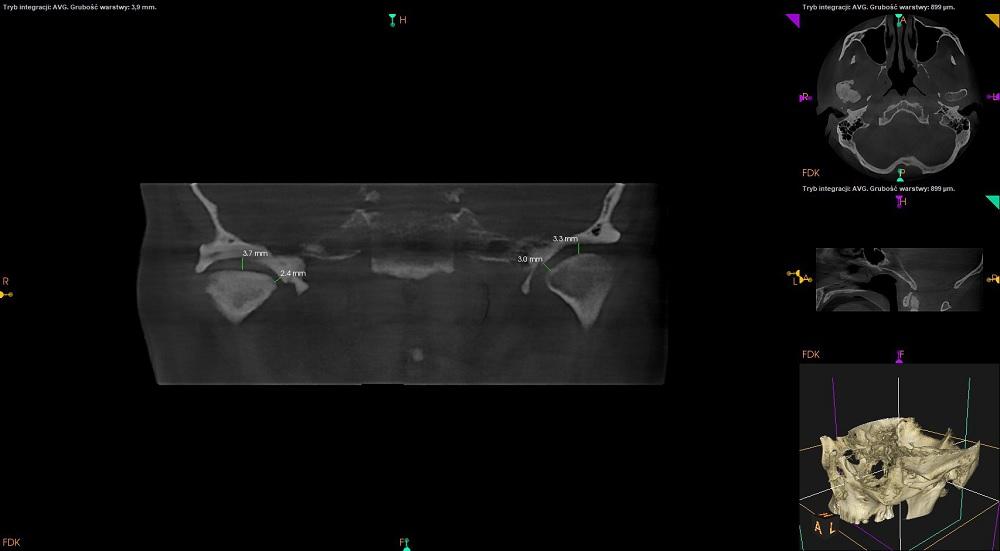

CBCT stawów skroniowo – żuchwowych w zwarciu.

Uwidoczniono zaawansowane zmiany zwyrodnieniowe w obrębie prawego stawu skroniowo – żuchwowego z objawami:

-szpara stawowa zwężona,

-występuje sklerotyzacja podchrzęstna powierzchni stawowych,

-powierzchnie stawowe spłaszczone,

-na przedniej powierzchni prawej głowy żuchwy osteofit, czyli wyrośla kostne.

Znaczna sklerotyzacja wyrostka kłykciowego wraz z przebudową zzś jest dobrze widoczna na przekroju strzałkowym.

Staw lewy :

Głowa żuchwy przesunięta w panewce do dołu i do przodu.

Kształt głowy żuchwy zaokrąglony, obrys regularny, bez zmian.